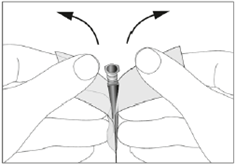

8. Öffnen Sie den Nadelbeutel an den Laschen (siehe Abbildung 1)

1